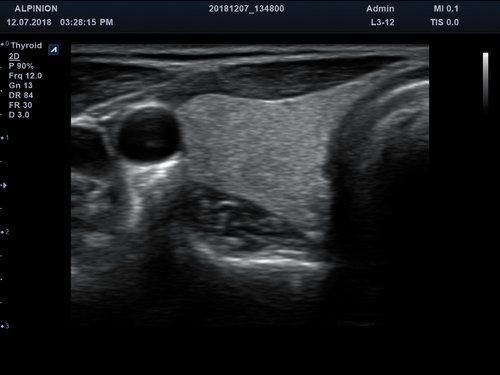

Das Alpinion minisono ist ein tragbares Hand-Ultraschallgerät, das eine sichere und schnelle Diagnostik u. a. in den Anwendungsbereichen Abdomen, MSK, Vaskulär, kleine Organe sowie Bauch und Brust bietet. An das minisono kann über USB-Kabel entweder eine Linear-Sonde oder eine Konvex-Sonde angeschlossen werden. Die komplette ultraschallspezifische Hardware ist in den Griffstücken integriert.

Anwendungsbereiche Abdomen MSK, Nerven, Karotis, periphere Gefäße, Schilddrüse, Mamma

Bildgebungs-Modi B-Modus, CF, M, PW, PD B-Modus, CF, M, PW, PD

• B-Modus: Darstellung zweidimensionale Bilder anatomischer Strukturen

• Filtered Tissue Harmonic Imaging: Bilder mit verbesserter Kontrastauflösung und deutlich reduziertem Rauschen durch Analyse der harmonischen Oberwellen

• Spatial Compounding Imaging: Technologie, die durch mehrere, kombinierte Abstrahlwinkel höhere Kontraste, weniger Artefakte und homogene Aufnahmen vom Nah- bis zum Fernfeld bietet